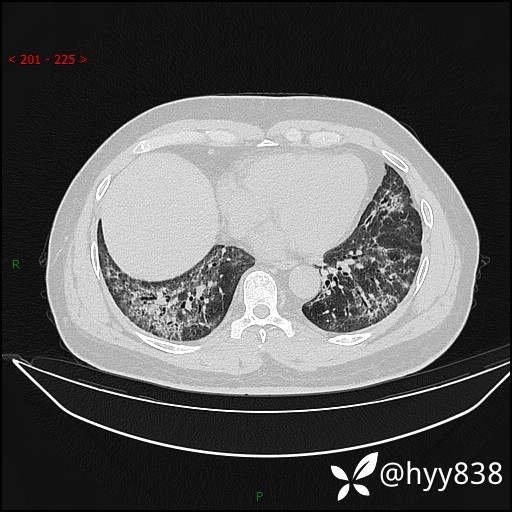

辅助检查:CT

临床诊断:间质性肺炎

第二次CT(7天后)